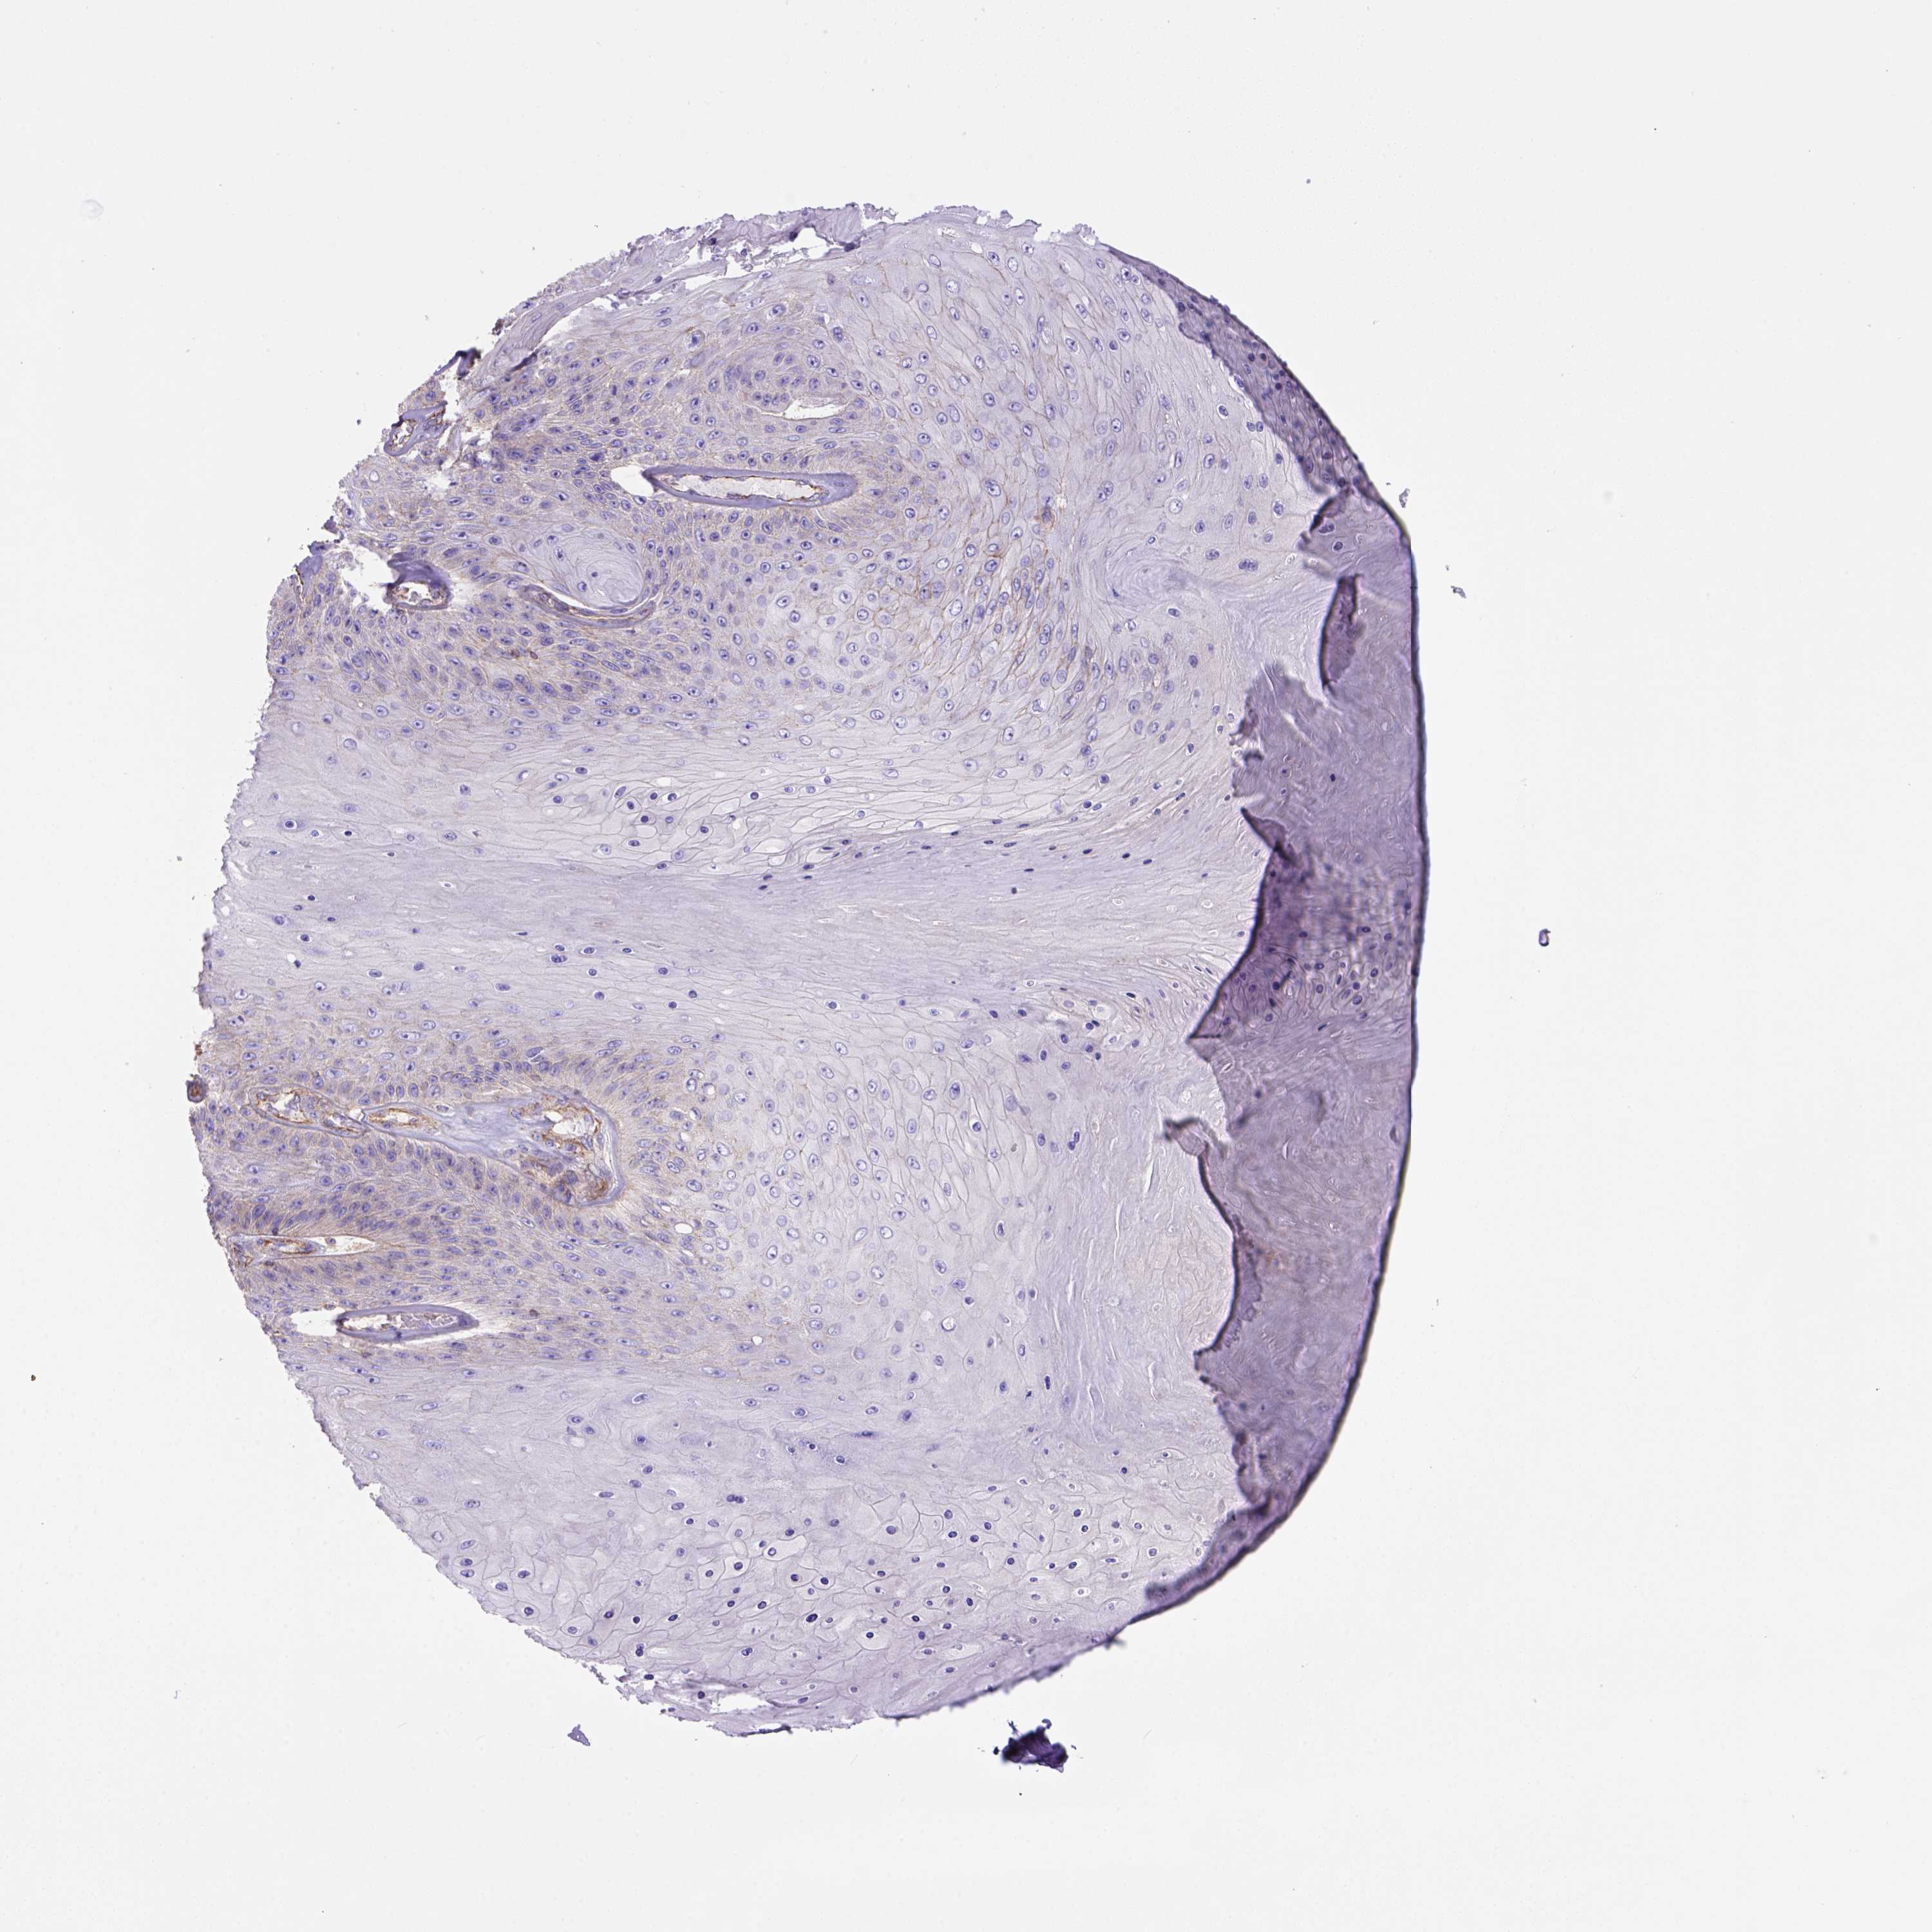

Basal cell and squamous cell cancer

SKIN CANCER - Protein expressioni

A mouse-over function shows sample information and annotation data. Click on an image to view it in a full screen mode. Samples can be filtered based on level of antibody staining by selecting one or several of the following categories: high, medium, low and not detected. The assay and annotation is described here.

Antibody stainingi

Antibody staining in the annotated cell types in the current human tissue is reported as not detected, low, medium, or high, based on conventional immunohistochemistry profiling in selected tissues. This score is based on the combination of the staining intensity and fraction of stained cells.

Each image is clickable and will lead to virtual microscopy that enables deeper exploration of all samples and also displays staining intensity scores, fraction scores and subcellular localization as well as patient and tissue information for each sample.

Antibody HPA069386

Staining

High

Medium

Low

Not detected

Intensity

Strong

Moderate

Weak

Negative

Quantity

>75%

75%-25%

<25%

None

Location

Nuclear

Cytoplasmic/membranous

Cytoplasmic/membranous,nuclear

Basal cell carcinoma

Squamous cell carcinoma, NOS